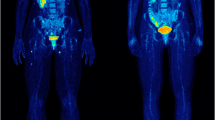

With regard to the quantitative parameters derived from physiologic non-tumoral tissues, SLR values were calculated in 66/67 patients (98.5%), since one patient had undergone splenectomy, while BLR values were calculated in all 67 patients (Table 2). The respective Kaplan–Meier curves demonstrated a trend for longer OS in patients with lower SLRmean values, although the log rank test revealed no statistical significance (p = 0.07) (Fig. 1A). None of the rest quantitative baseline parameters had a significant effect on patient OS (Table 3).

The values of quantitative parameters derived from physiologic non-tumoral tissues on interim PET/CT are presented in Table 2. The respective survival analysis revealed a significantly longer OS for patients with lower than median SLRmean (p = 0.02) and BLRmean (p = 0.01) (Table 3) (Fig. 1B).

The values of the quantitative parameters derived from physiologic non-tumoral tissues on late PET/CT imaging are presented in Table 2. Survival analysis revealed a significantly longer OS for patients with lower SLRmean values (p = 0.02) (Fig. 1C). The aggregated results of survival analysis based on quantitative data from physiologic non-tumoral tissues are presented in Table 3.

In this study we investigated the prognostic value of [18F]FDG PET/CT as part of response monitoring in metastatic melanoma patients treated with ICIs. The main findings of our analysis are the following: firstly, metabolic response based on [18F]FDG PET/CT, performed after four cycles of immunotherapy, is significantly associated with OS after application of different metabolic criteria. Secondly, the modality also carries significant prognostic information on patient survival already after administration of the first two ICIs’ cycles, especially with employment of the novel immunotherapy-modified PERCIMT. Thirdly, the assessment of immune activation signs in the spleen may have a potential role as prognosticator, as reflected by the longer survival of patients exhibiting a low SLRmean throughout the course of immunotherapy. On the other hand, the emergence of PET signs of irAEs is not associated with patient survival.

Apart from the assessment of treatment response based on the evaluation of tumor lesions, our analysis also involved the investigation of signs of immune activation on PET as a supplementary approach for prediction of the immunotherapy effect. We, specifically, performed semi-quantitative calculations of [18F]FDG uptake in two immune organs, namely the spleen and the bone marrow, and derived spleen-to-liver (SLR) and bone marrow-to-liver (BLR) ratios. Herein, the principal finding was the association between SLRmean and patient survival. In particular, patients with lower SLRmean values exhibited a longer OS, a result that was consistent throughout the duration of follow-up. Ascertaining the role of spleen metabolism during immunotherapy has proved to be a challenging task, with the so far published results on the interpretation of this phenomenon being rather inconclusive. Indeed, on the one hand, the present results are in line with previous works [22, 33, 38] suggesting that an increased spleen metabolism on [18F]FDG PET/CT correlates with an unfavorable patient outcome. On the other hand, in a prospective study of [18F]FDG PET/MRI in melanoma patients under ICIs, a significant increase in spleen metabolism (SULmean) was observed as early as two weeks after treatment initiation in responders, in contrary to non-responders who showed stability of the parameter [39]. In this context, although our results highlight the potential role of SLRmean as prognosticator, they should be interpreted with caution. Overall, however, the investigation by functional imaging not only of the tumor but also the host’s immune system is gradually gaining importance as a potential surrogate marker of therapeutic response. Future prospective studies should determine whether this approach could indeed serve as a prognostic indicator of immunotherapy.